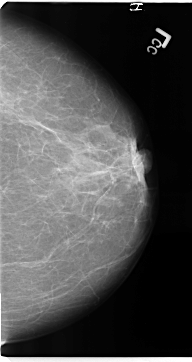

B_3137_1.LEFT_CC

LEFT_CC LINES 4704 PIXELS_PER_LINE 2496 BITS_PER_PIXEL 12 RESOLUTION 50 NON_OVERLAY